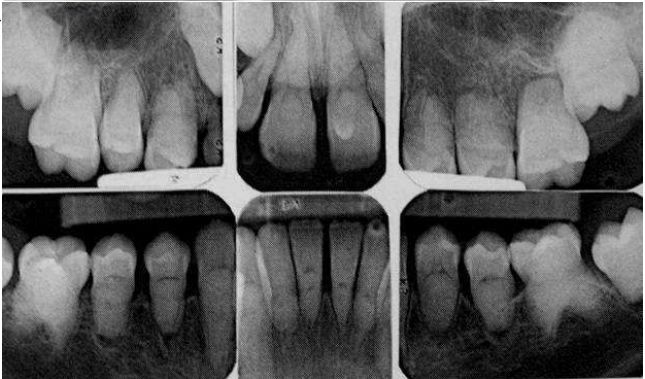

69.下列何者可診斷為牙本質發育不良(dentin dysplasia) ? (A) (B)(C)(D)

75.附圖中X光影像最符合下列何種疾病的病徵? (A)牙本質形成不良(dentinogenesis imperfecta) (B)牙本質發育不良第一型(dentin dysplasia type I) (C)牙本質發育不良第二型(dentin dysplasia type II) (D)牙中牙(dens in dente)